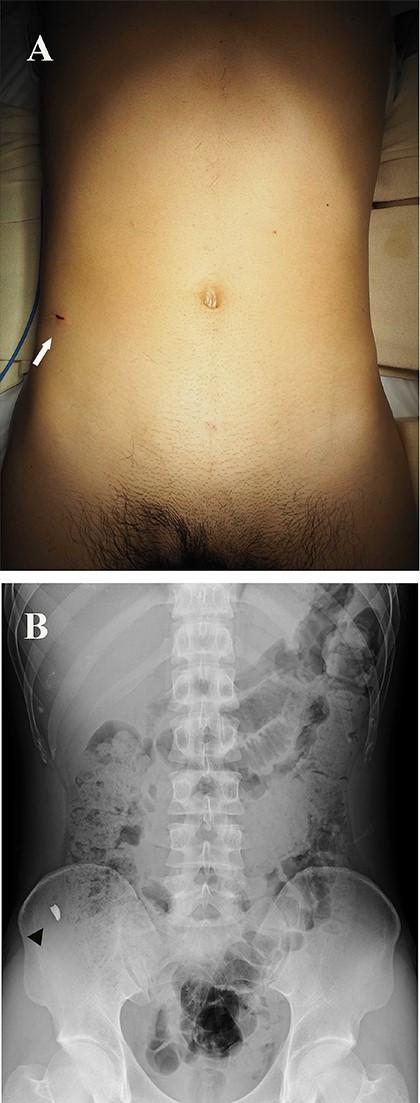

A 27-year-old man working in a forging factory presented to our hospital with acute abdominal pain. He reported that, 3 hours before presentation, a metal fragment came flying from the operating power hammer, which molded molten metal into the desired shape by striking it. Although he was wearing protective clothing, the fragment penetrated through it and caused sharp pain. Physical examination revealed a 1 cm wound, resembling a stab wound above the right iliac crest (Fig. 1A). The patient experienced localized abdominal pain around the wound; however, there were no signs of peritoneal irritation. His vital signs were stable and laboratory data showed no abnormalities except for a slightly increased C-reactive protein level of 0.91 mg/dL (reference range, 0–0.14). A spine abdominal radiograph showed a 1 cm-sized radiopaque object in the lower right abdomen (Fig. 1B). An abdominal computed tomography revealed a radiopaque object near the peritoneum; however, its exact location being extraperitoneal or intraperitoneal could not be determined (Fig. 2A and B). The abdominal cavity did not have free air or fluid retention. The patient was diagnosed to have a foreign body near the peritoneum and surgical removal was planned. The operation was performed using single-incision plus one-port laparoscopic surgery (SILS plus one). A 1.5 cm longitudinal incision was made at the umbilicus to access the abdominal cavity, after which the wound retractor (Smart Retractor XS; TOP Corp., Tokyo, Japan) was inserted. It was mounted to a single-port access device (Free Access; TOP Corp., Tokyo, Japan). Subsequently a 5-mm trocar was placed just above the pubic symphysis. Laparoscopic inspection following pneumoperitoneum revealed no damage to the peritoneum or internal organs (Fig. 3A). Although we assumed the foreign body was located in the abdominal wall, laparoscopic inspection could not confirm its position. Real-time fluoroscopy was used to locate the fragment. The nearest peritoneum was incised and the abdominal muscle was dissected until the foreign body was observed (Fig. 3B). It was found embedded in the transversus abdominis muscle (Fig. 3C) and was safely removed using forceps (Fig. 3D). The object was 1.5 cm long and sharp at both ends (Fig. 4). The patient was discharged from our hospital after a good postoperative course.

Abdominal CT showing a radiopaque object near the peritoneum. (A) coronal view; (B) sagittal view (arrows).